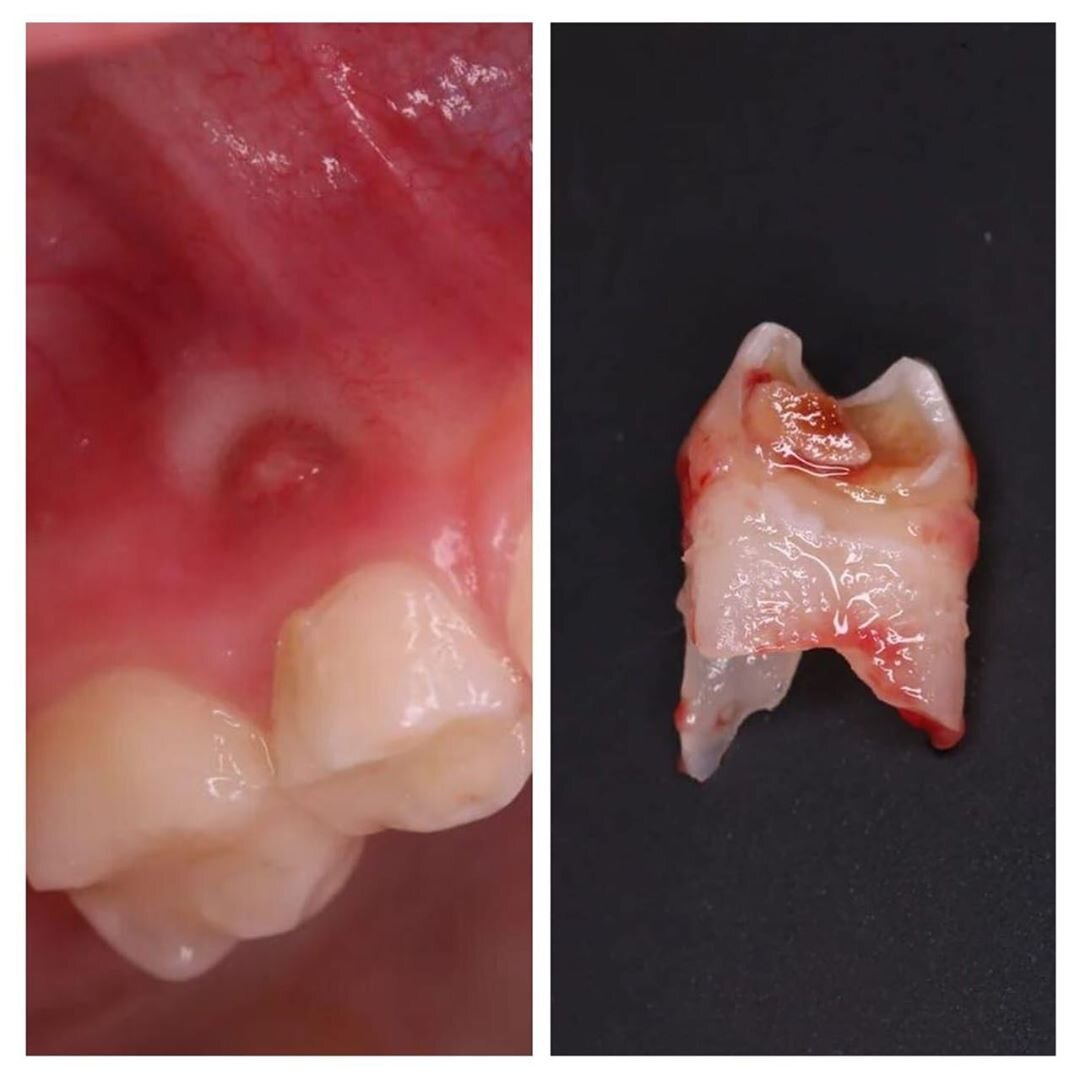

К сожалению, четвертый зуб пришлось удалить.

Видите "прыщик" над десной?

Это свищевой ход или попросту свищ.

Молочная "четверка" ранее была пролечена, но снова поражена кариесом.

Процесс не виден наглядно, только снимок помог прояснить картину целиком.

Воспаление ушло вглубь и перешло на соседние ткани - периодонт.

Диагноз - периодонтит молочного зуба.

Именно из-за него на десне вылез свищ.

И это абсолютное показание для удаления.

Работу проводила детский стоматолог Гуля Билялова.

Под местной анестезией зубик был удален.